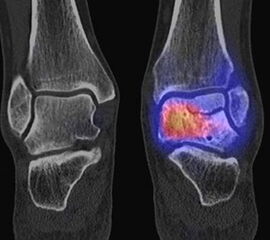

Abbildung 1.8.a und b: Akute Arthritis bei bekannter Gicht in beiden OSG: links die Früh-/Weichteilphase; rechts die Mineralisations­phase. Deutliche, entzündlich bedingte Mehranreicherungen in der Früh-/Weichteilphase. In der Mineralisation­sphase erkennt man die entzündliche Mitreaktion der subchondralen Gelenkabschnitte.

Abbildung 1.8.c - e: Akute Arthritis in beiden OSG, rechts > links. Im SPECT/CT erkennt man die Mitreaktion der subchondralen Gelenkabschnitte. Die Arthritis ist so akut, dass (noch) keine ossären morphologischen Veränderungen im CT abgrenzbar sind.

Zum Lesen der Bildbeschreibung und zur Vollansicht bitte die Bilder anklicken. Bilder: H. C. Rischke